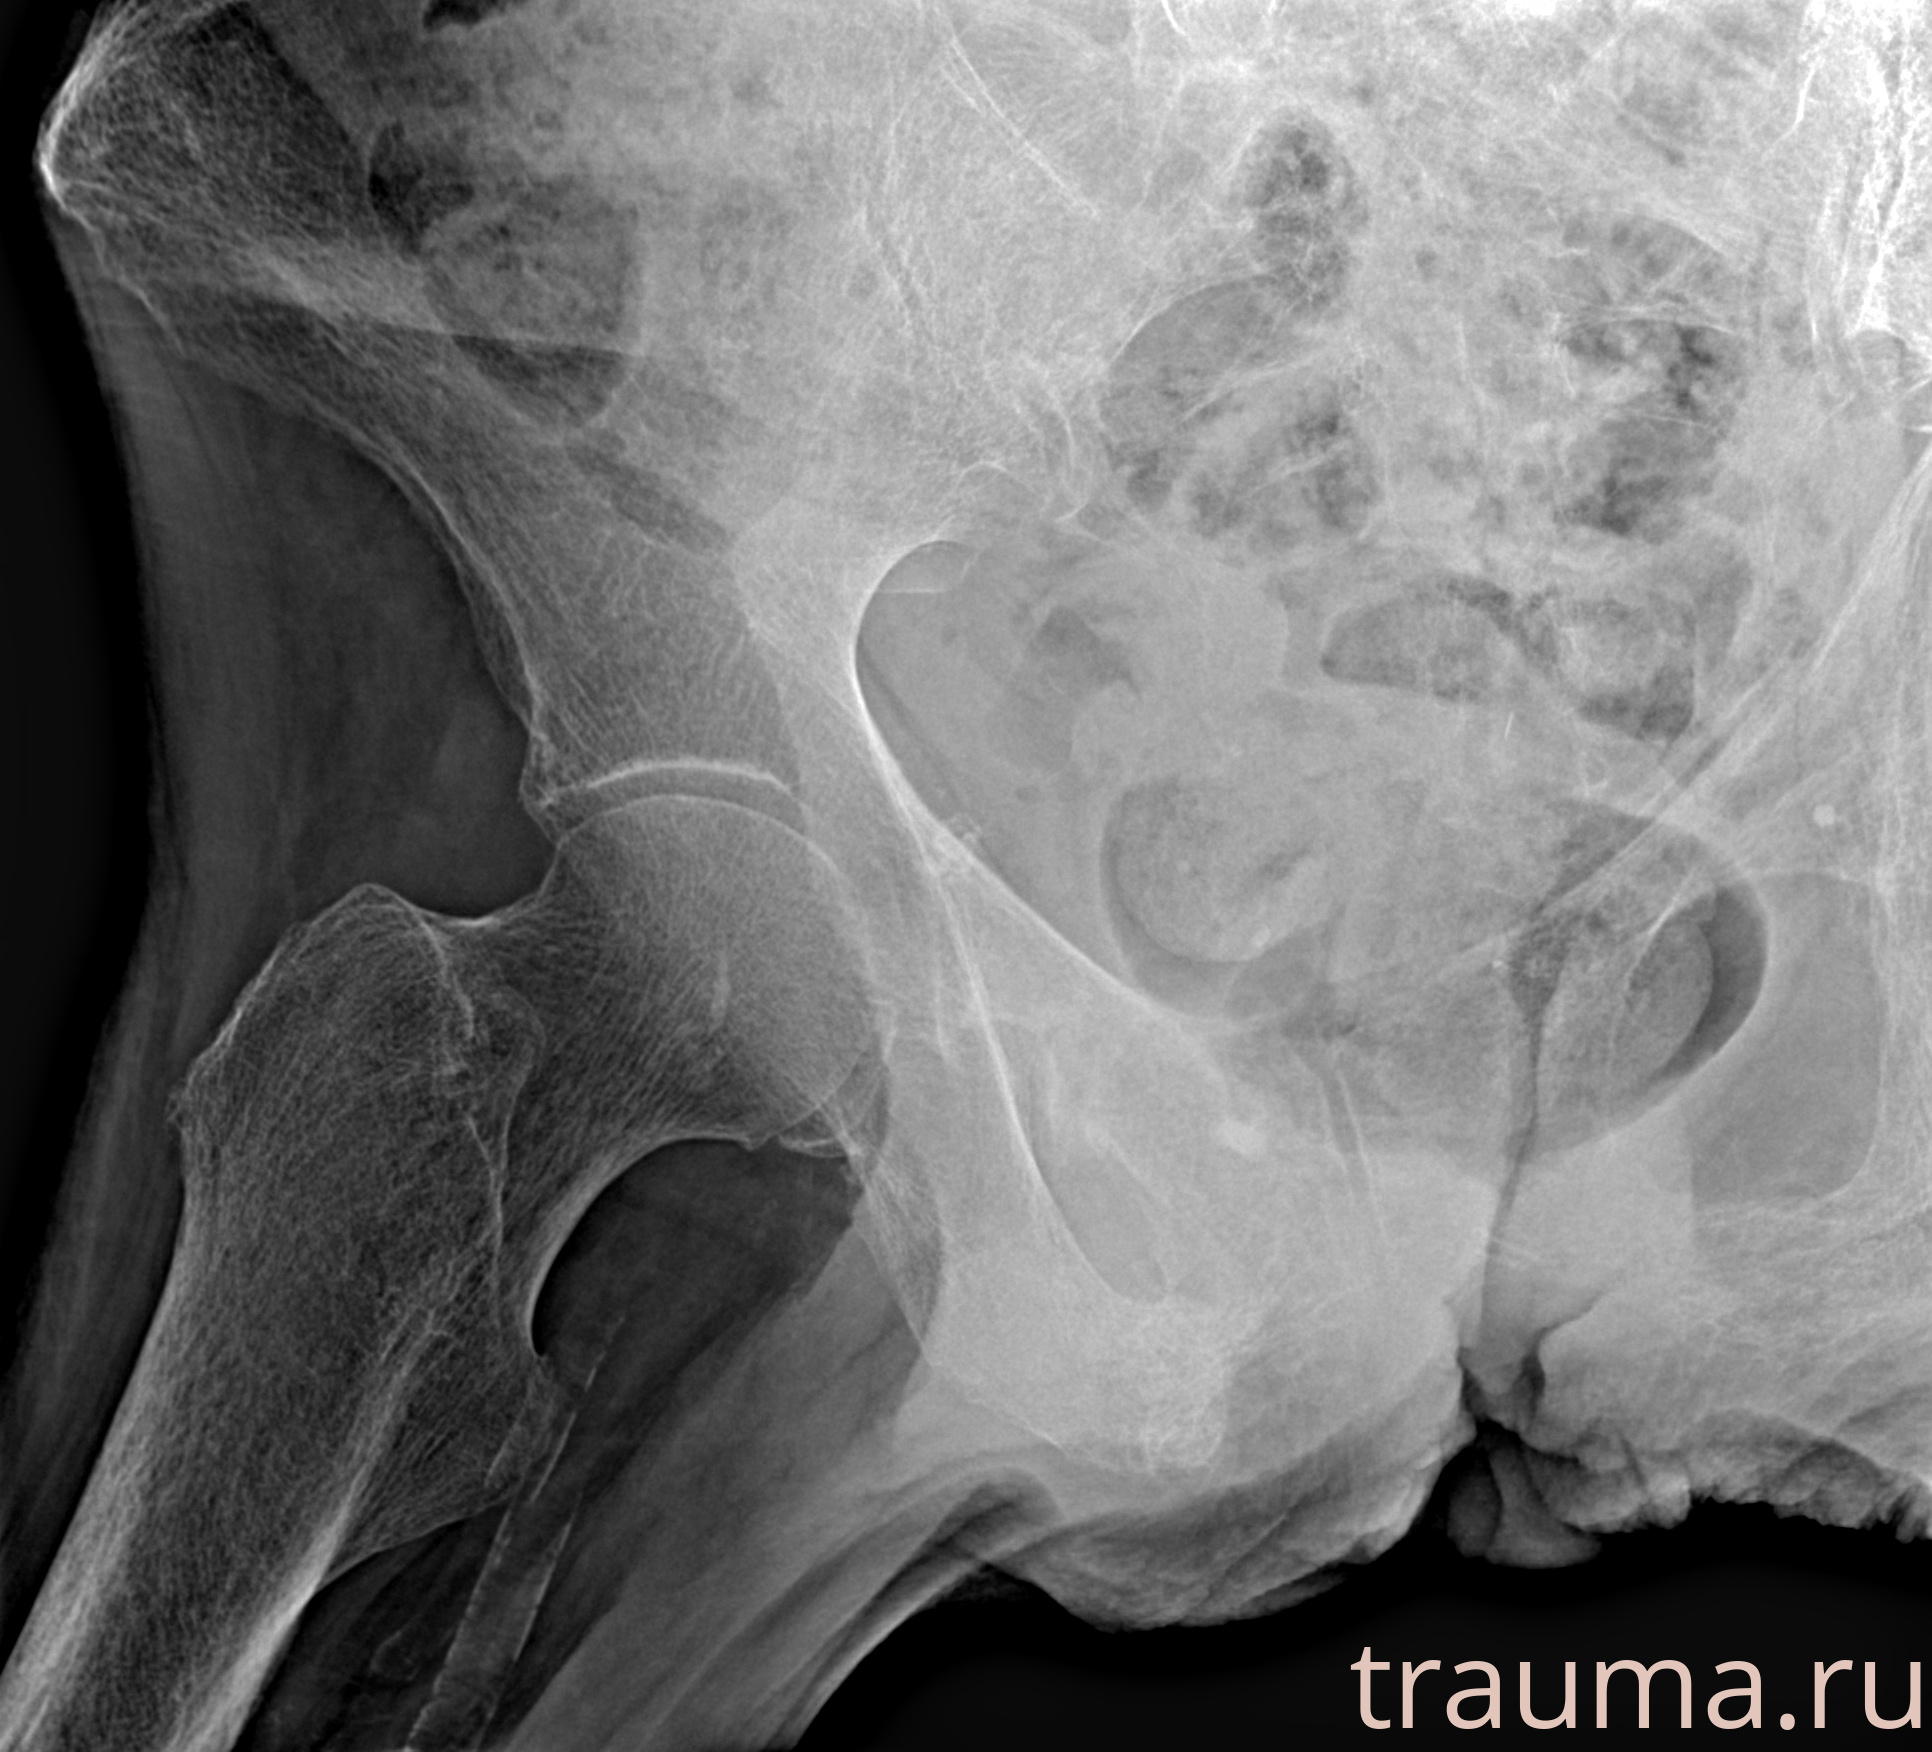

Рентген на дому: по вашему адресу приезжает врач-рентгенолог, травматолог-ортопед с мобильным рентгеновским аппаратом, проводит диагностику травмы или заболевания, делает необходимые рентгенограммы, дает рекомендации по дальнейшему лечению. Получить качественные снимки в домашних условиях возможно благодаря уникальной методике, разработанной МосРентген Центром для института  Склифосовского

при переломе шейки бедра и пневмонии от компании МосРентген Центр - партнера Института имени Склифосовского